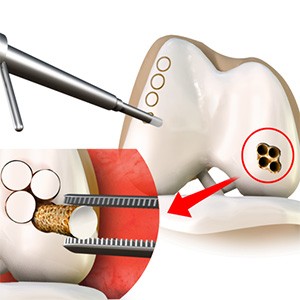

Subchondroplasty

Subchondroplasty is a minimally invasive procedure that is performed to specifically repair chronic BMLs by filling them with a bone substitute material. The bone substitute is then slowly resorbed and replaced with healthy bone, repairing the bone defect.